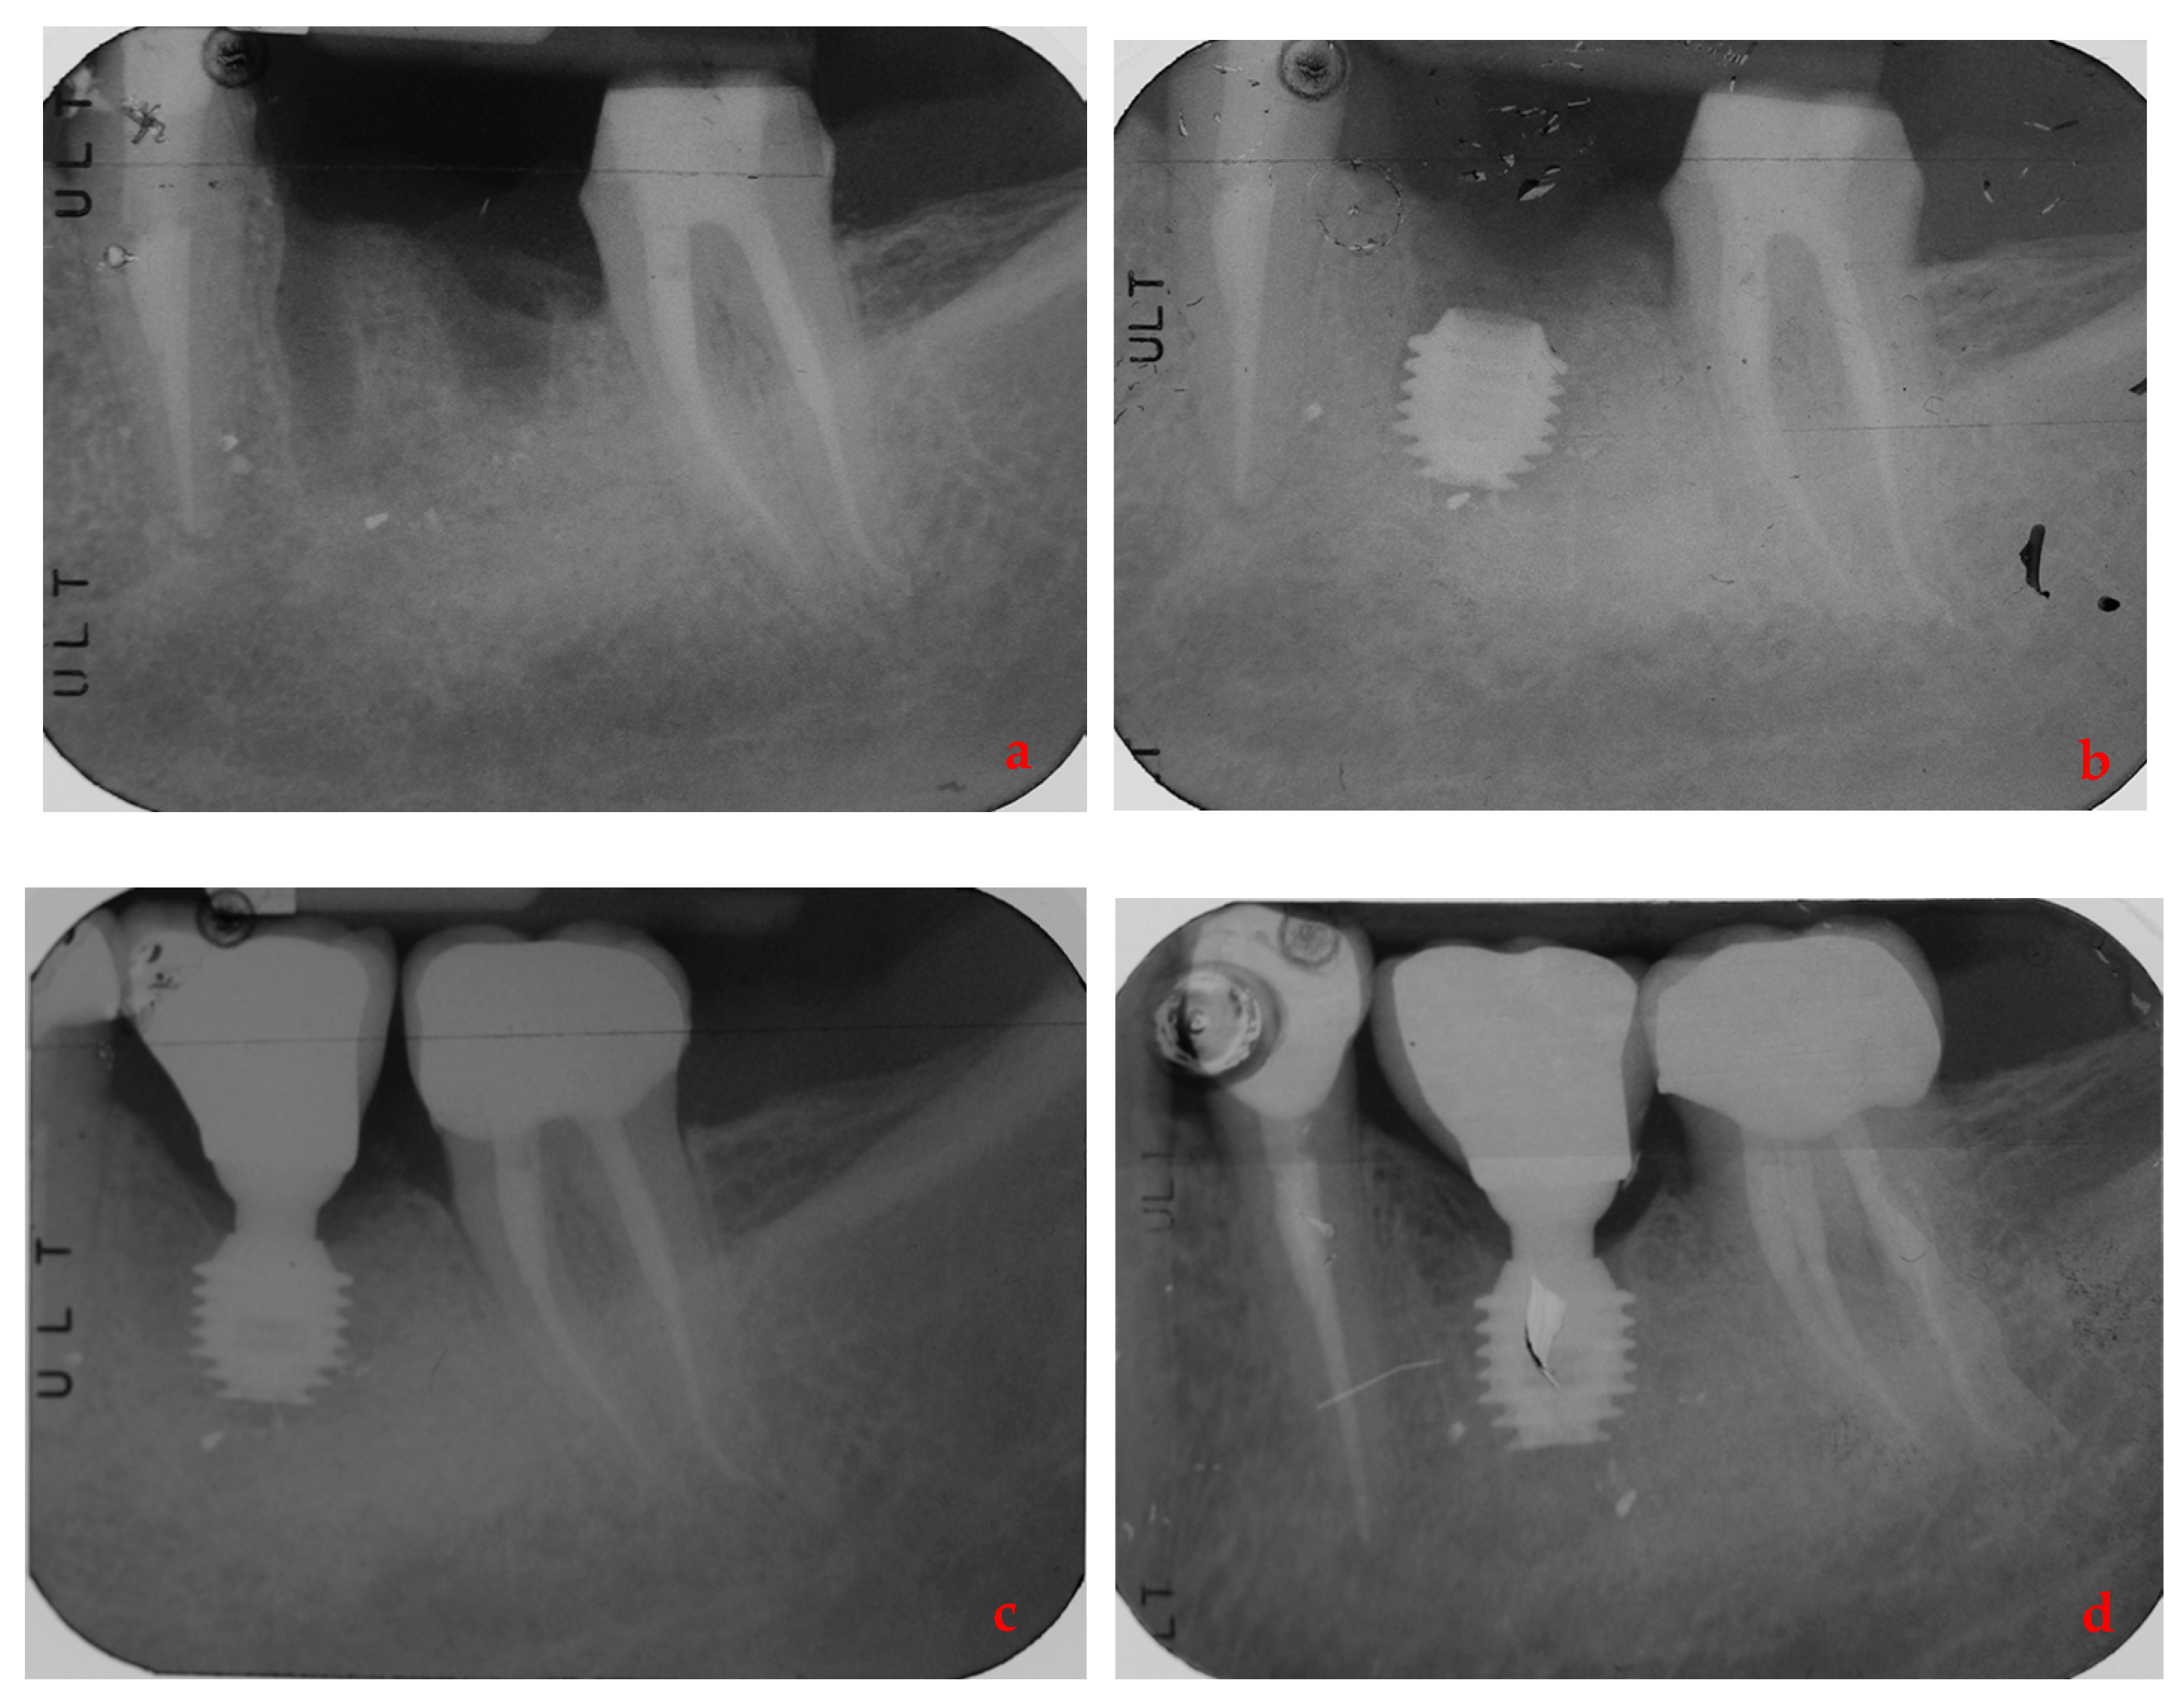

- Lombardo, G.; Signoriello, A.; Simancas-Pallares, M.; Marincola, M.; Nocini, P.F. Survival of Short and Ultra-Short Locking-Taper Implants Supporting Single Crowns in the Posterior Mandible: A 3-Year Retrospective Study. J. Oral Implant. 2020, 46, 396–406. [Google Scholar] [CrossRef] [PubMed]

- Lombardo, G.; Marincola, M.; Signoriello, A.; Corrocher, G.; Nocini, P.F. Single-Crown, Short and Ultra-Short Implants, in Association with Simultaneous Internal Sinus Lift in the Atrophic Posterior Maxilla: A Three-Year Retrospective Study. Materials 2020, 13, 2208. [Google Scholar] [CrossRef] [PubMed]